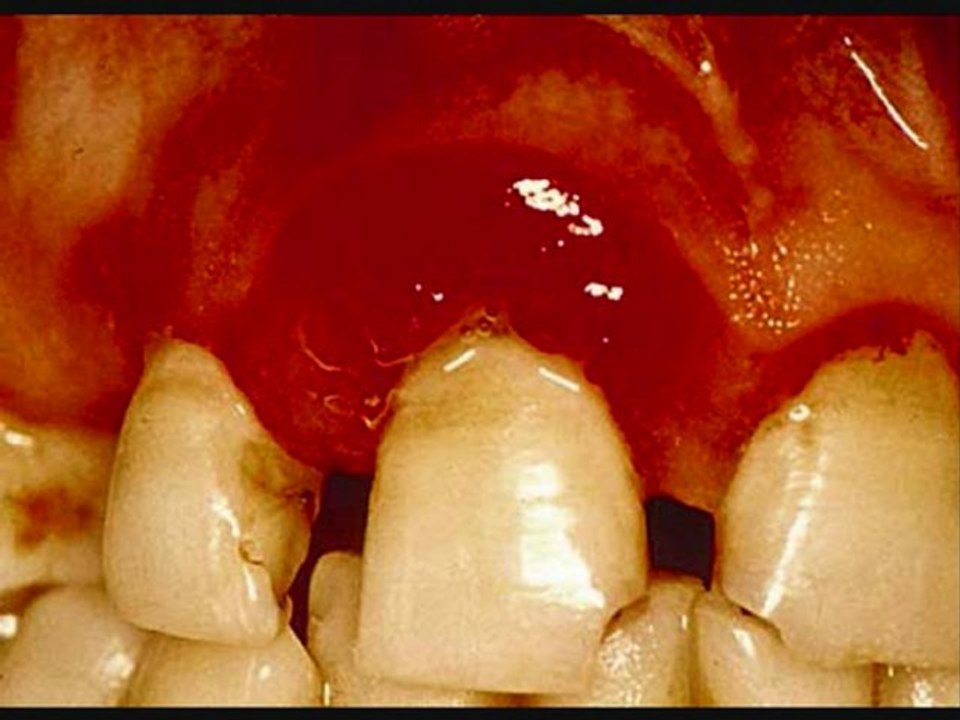

http://www.trustedgumproducts.com Stop Gum Disease - Gum Disease Stop To Stop Gum Disease. Get real info on stopping gum disease. Understanding the basics of Stopping Gum disease goes a long way toward healthy oral hygiene habits that Stop Gum Disease. Stopped Gum Disease is an extremely common condition, affecting about 90% of the U.S. population. It is a mild form of gum disease in which gums become inflamed and swollen and prone to bleeding easily. Gum disesase usually brings minimal, physical discomfort; however, if left alone, it places you at risk for a host of more severe gum diseases.